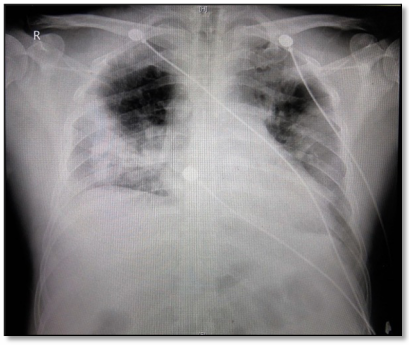

患者主诉“发作性胸痛8个月,加重2周,胸闷气促1周”。8个月前无明显诱因感心前区疼痛,针刺样,持续时间短。无放射痛,口服麝香保心丸可缓解。2022年6月至我院心内科就诊,冠脉造影提示冠脉狭窄,拒绝支架植入,近2周胸痛加重,双下肢水肿加重,1周前出现胸闷气急进行性加重,不能平稳,咳嗽咳血性分泌物,外院给予无创通气治疗,1天前急诊收治我院心内科监护室。入院诊断“冠心病,高血压病3级,2型糖尿病,脑梗死后遗症”。胸片显示心脏增大,两肺渗出明显。

图片